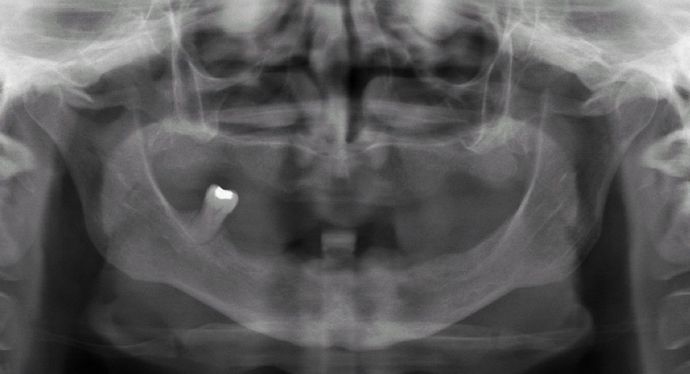

This healthcare professional unfortunately had gum disease early on in her life and was given a top denture and was unhappy with her lower partial. She was trying to hold on to the very last tooth to avoid wearing a lower denture. She had consulted many doctors who told her that she had no bone for dental implants and would need major bone grafting procedures. Dr. Bidra identified areas of available bone using a CT scan, and successfully performed the All on 4 procedure on upper and lower (top and bottom) without the need for any bone grafting, and gave her fixed permanent zirconia bridges.

Procedures : extractions, implants, All on 4 , Teeth in a day, no bone grafting and full mouth reconstruction with monolithic zirconia bridges.